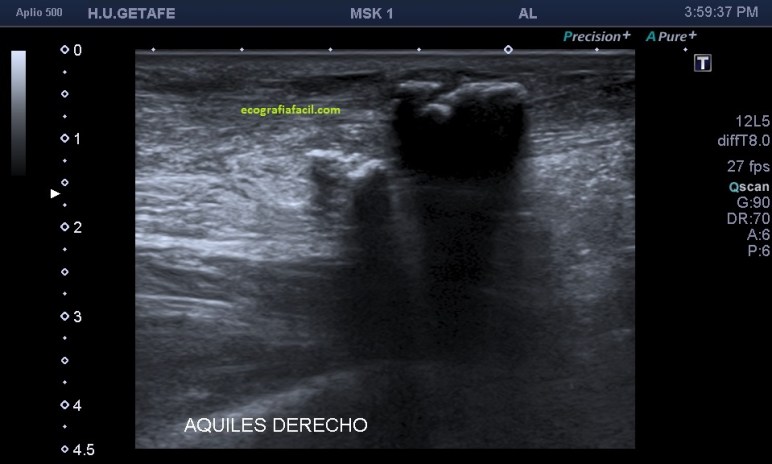

La aparición de estas calcificaciones me llevó a pensar que la presencia de calcio pudiese corresponder a avulsiones de materíal óseo correspondiente al calcáneo, es decir, roturas del Aquiles con arrancamiento de la inserción del hueso. En muchas ocasiones el tendón de aquiles calcifica en su inserción, normalmente son calcificaciones lineales que están en relación con tendinopatías de inserción, entensopatías, pero en ocasiones estas calcificaciones son muy evidentes, y existe cambios que tanto ecográficamente como físicamente afectan a esta la región y pueden aparecer bultomas y enrojecimiento de la zona, en relación con el síndrome de Haglund.

En el texto anterior hemos visto enmarañadamente muchos conceptos asociados a patologías que pueden darse en esta pequeña región del Aquiles. He nombrado el Síndrome de Haglund. Este es un síndrome que incluye tres aspectos, a nivel del aspecto posterior del calcáneo con una afectación de la bursa retroaquílea debido a la presencia de una exóstosis.

Si observamos la bursitis retroaquílea de la imagen 11(flechas amarillas), además la exóstosis de la imagen 13 y deformidad en la piel, observable sin ecografía podemos estar ante un síndrome de Haglund de esos de libro…y tendremos una imagen ecográfica como la de la imagen 14.

La flecha amarilla indica la que en la parte posterior del calcáneo existe un calcio tosco en esta rx lateral del pie en carga, pero es en la inserción, cuidado con esto, cuando se produce el Haglund, no es en la inserción, es antes, y se debe a la exostosis mencionada con anterioridad, mira, compara imagen 12 e imagen 13. La flecha roja es indicativa de Síndrome de Haglund.

En la imagen 14, como no podía ser de otra manera, observamos todo y es por definición la típica imagen de S.Haglund.